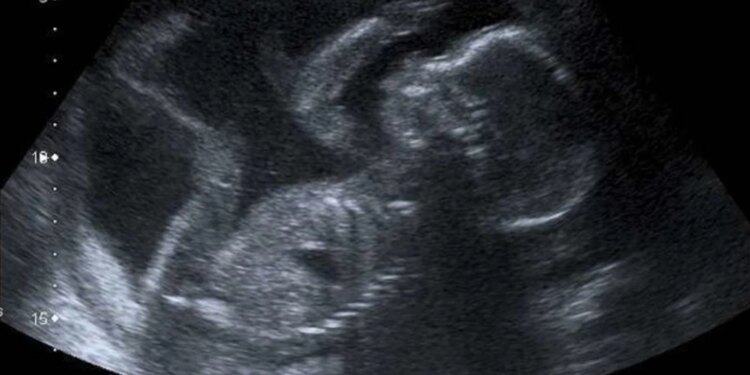

Ultrasonido de un bebé a las 20 semanas de gestación. / Crédito: Steve vía Flickr (CC BY-NC 2.0).